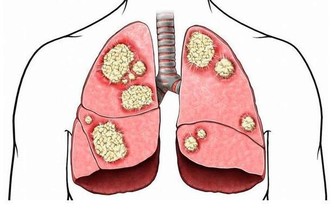

儘管低密度脂蛋白膽固醇的含量較低,通常意味著一個人較為健康,但一項新的臨床資料顯示,一些癌症患者體內的低密度脂蛋白膽固醇含量也非常低。研究發現,血液中低密度脂蛋白膽固醇含量過低的人容易出現各種感染,被感染的持續時間較長,可能誘發癌症。